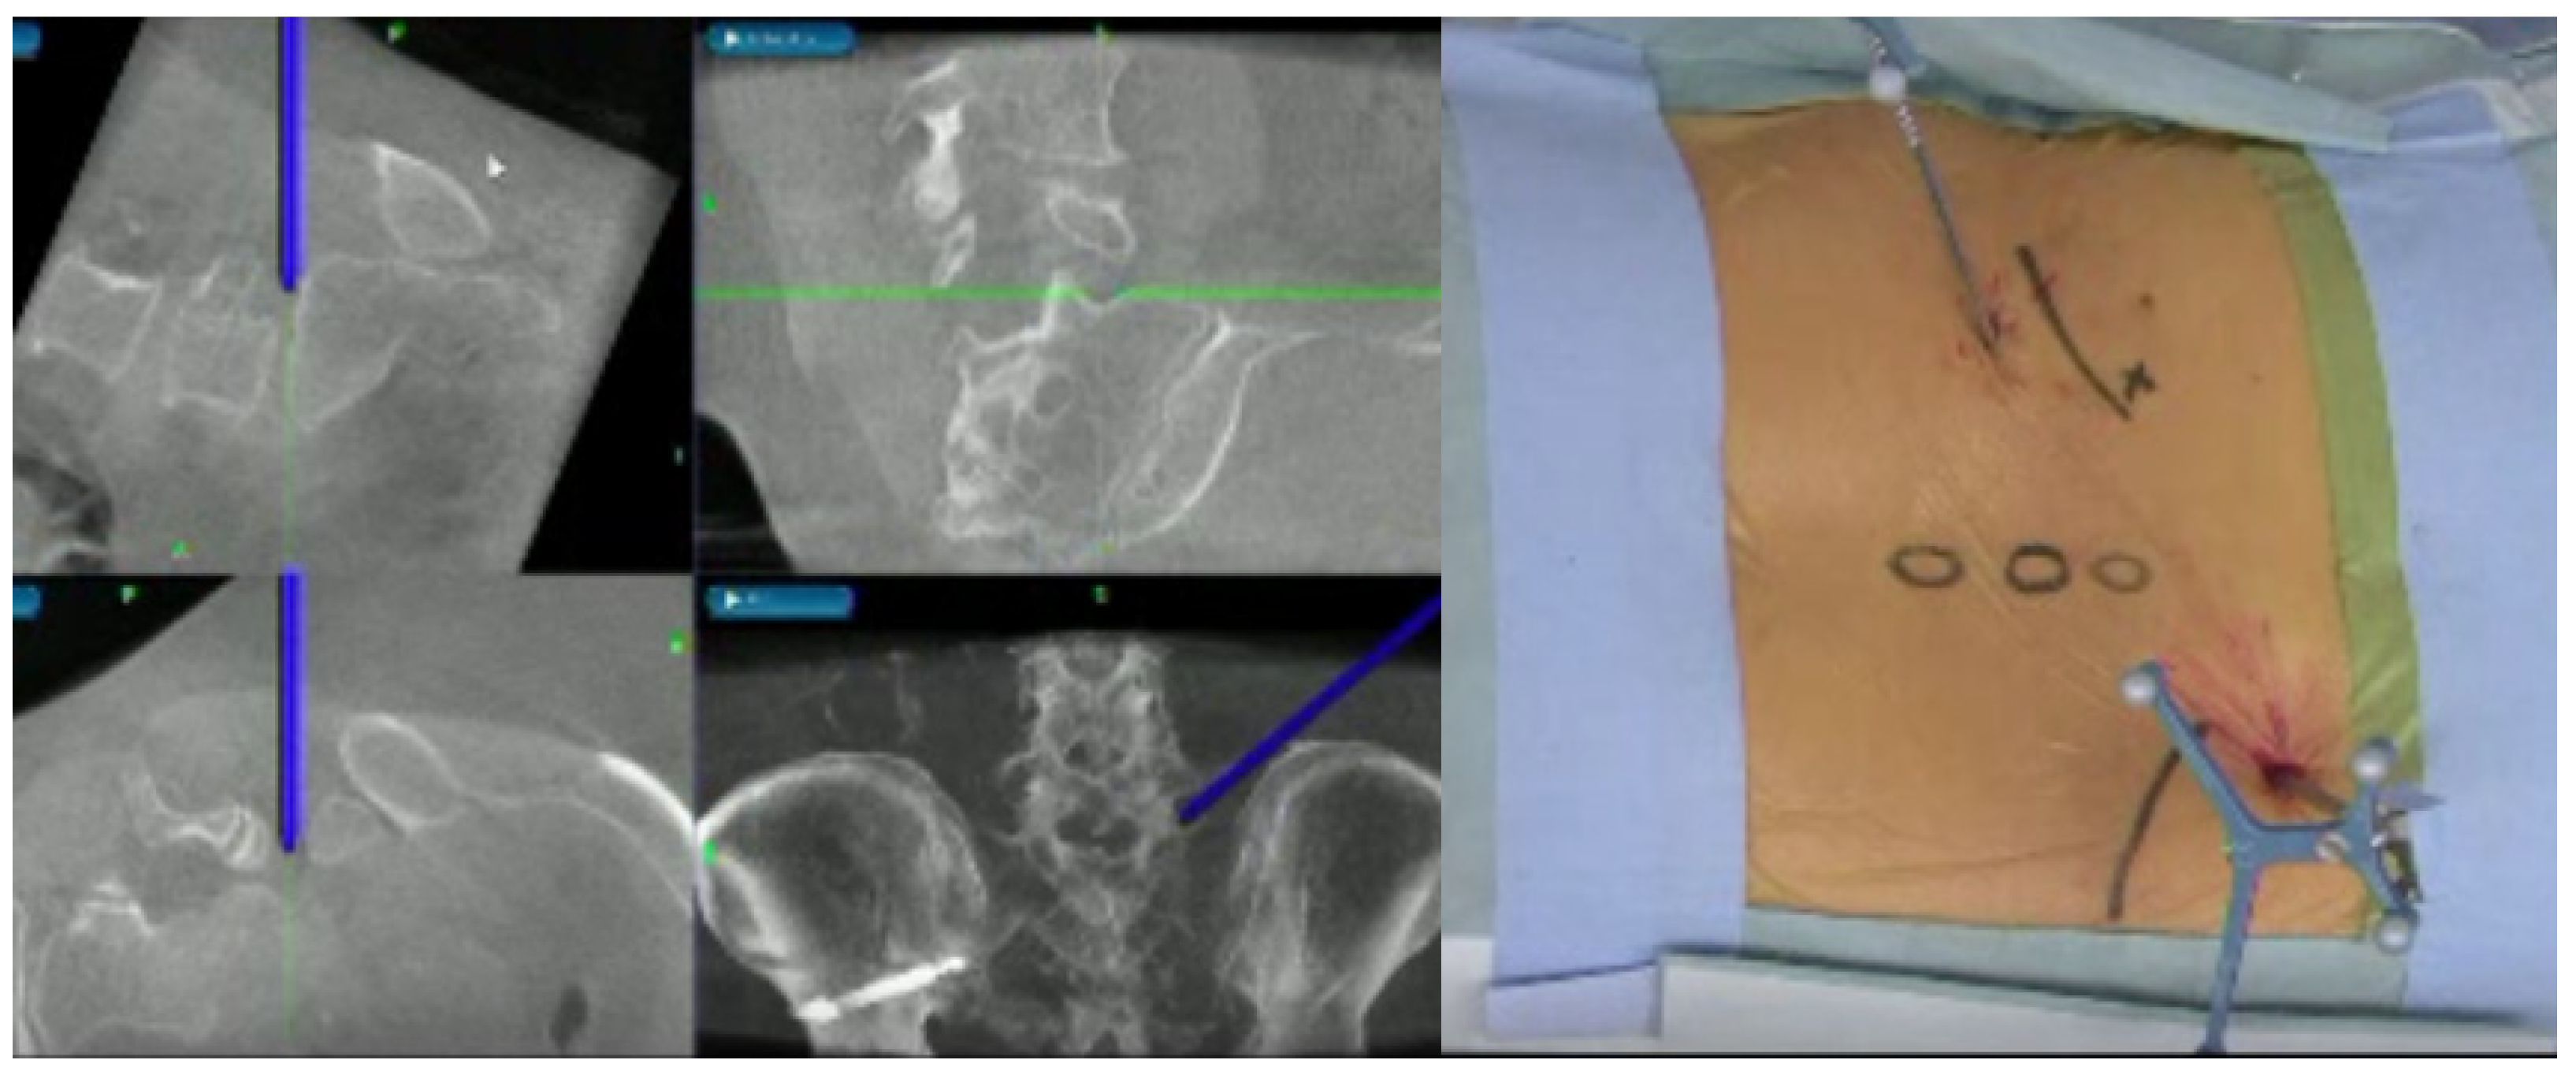

2.2. Image Technique

2.3. CT-MRI Fusion Image

2.4. Evaluation of Merged Images